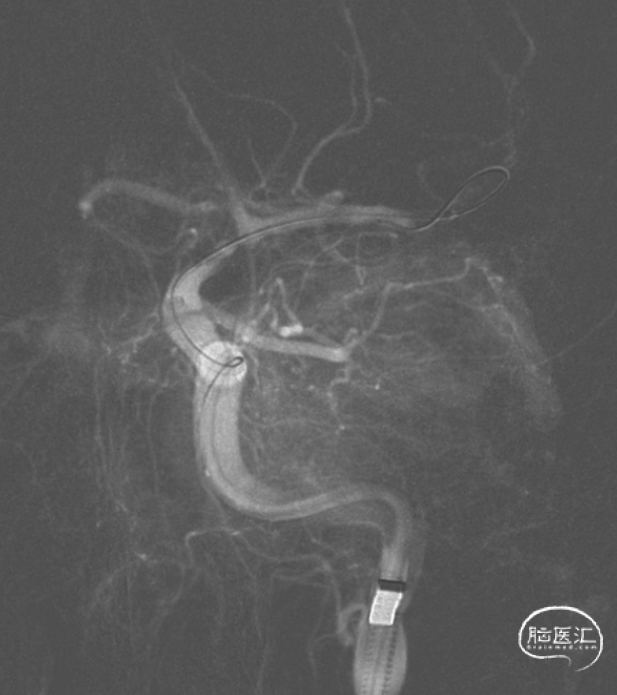

球囊扩张1次,狭窄较前改善,停留10分钟观察,狭窄段血管未见明显回缩,最终造影提示闭塞段血流恢复,mTICI 3级。

残余狭窄,考虑到手术风险,拟二期支架置入。

术后4小时麻醉复苏,肢体功能恢复良好。

术后CT,未见明显出血或梗死。